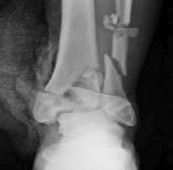

Figures 1 and 2 are the radiographs of a 68-year-old woman who comes to the emergency department after stepping into a hole and twisting her ankle. She is complaining of isolated ankle pain and is unable to bear weight.

After closed manipulative reduction and splint placement, she is scheduled for operative treatment. The stability of the syndesmosis should be evaluated after